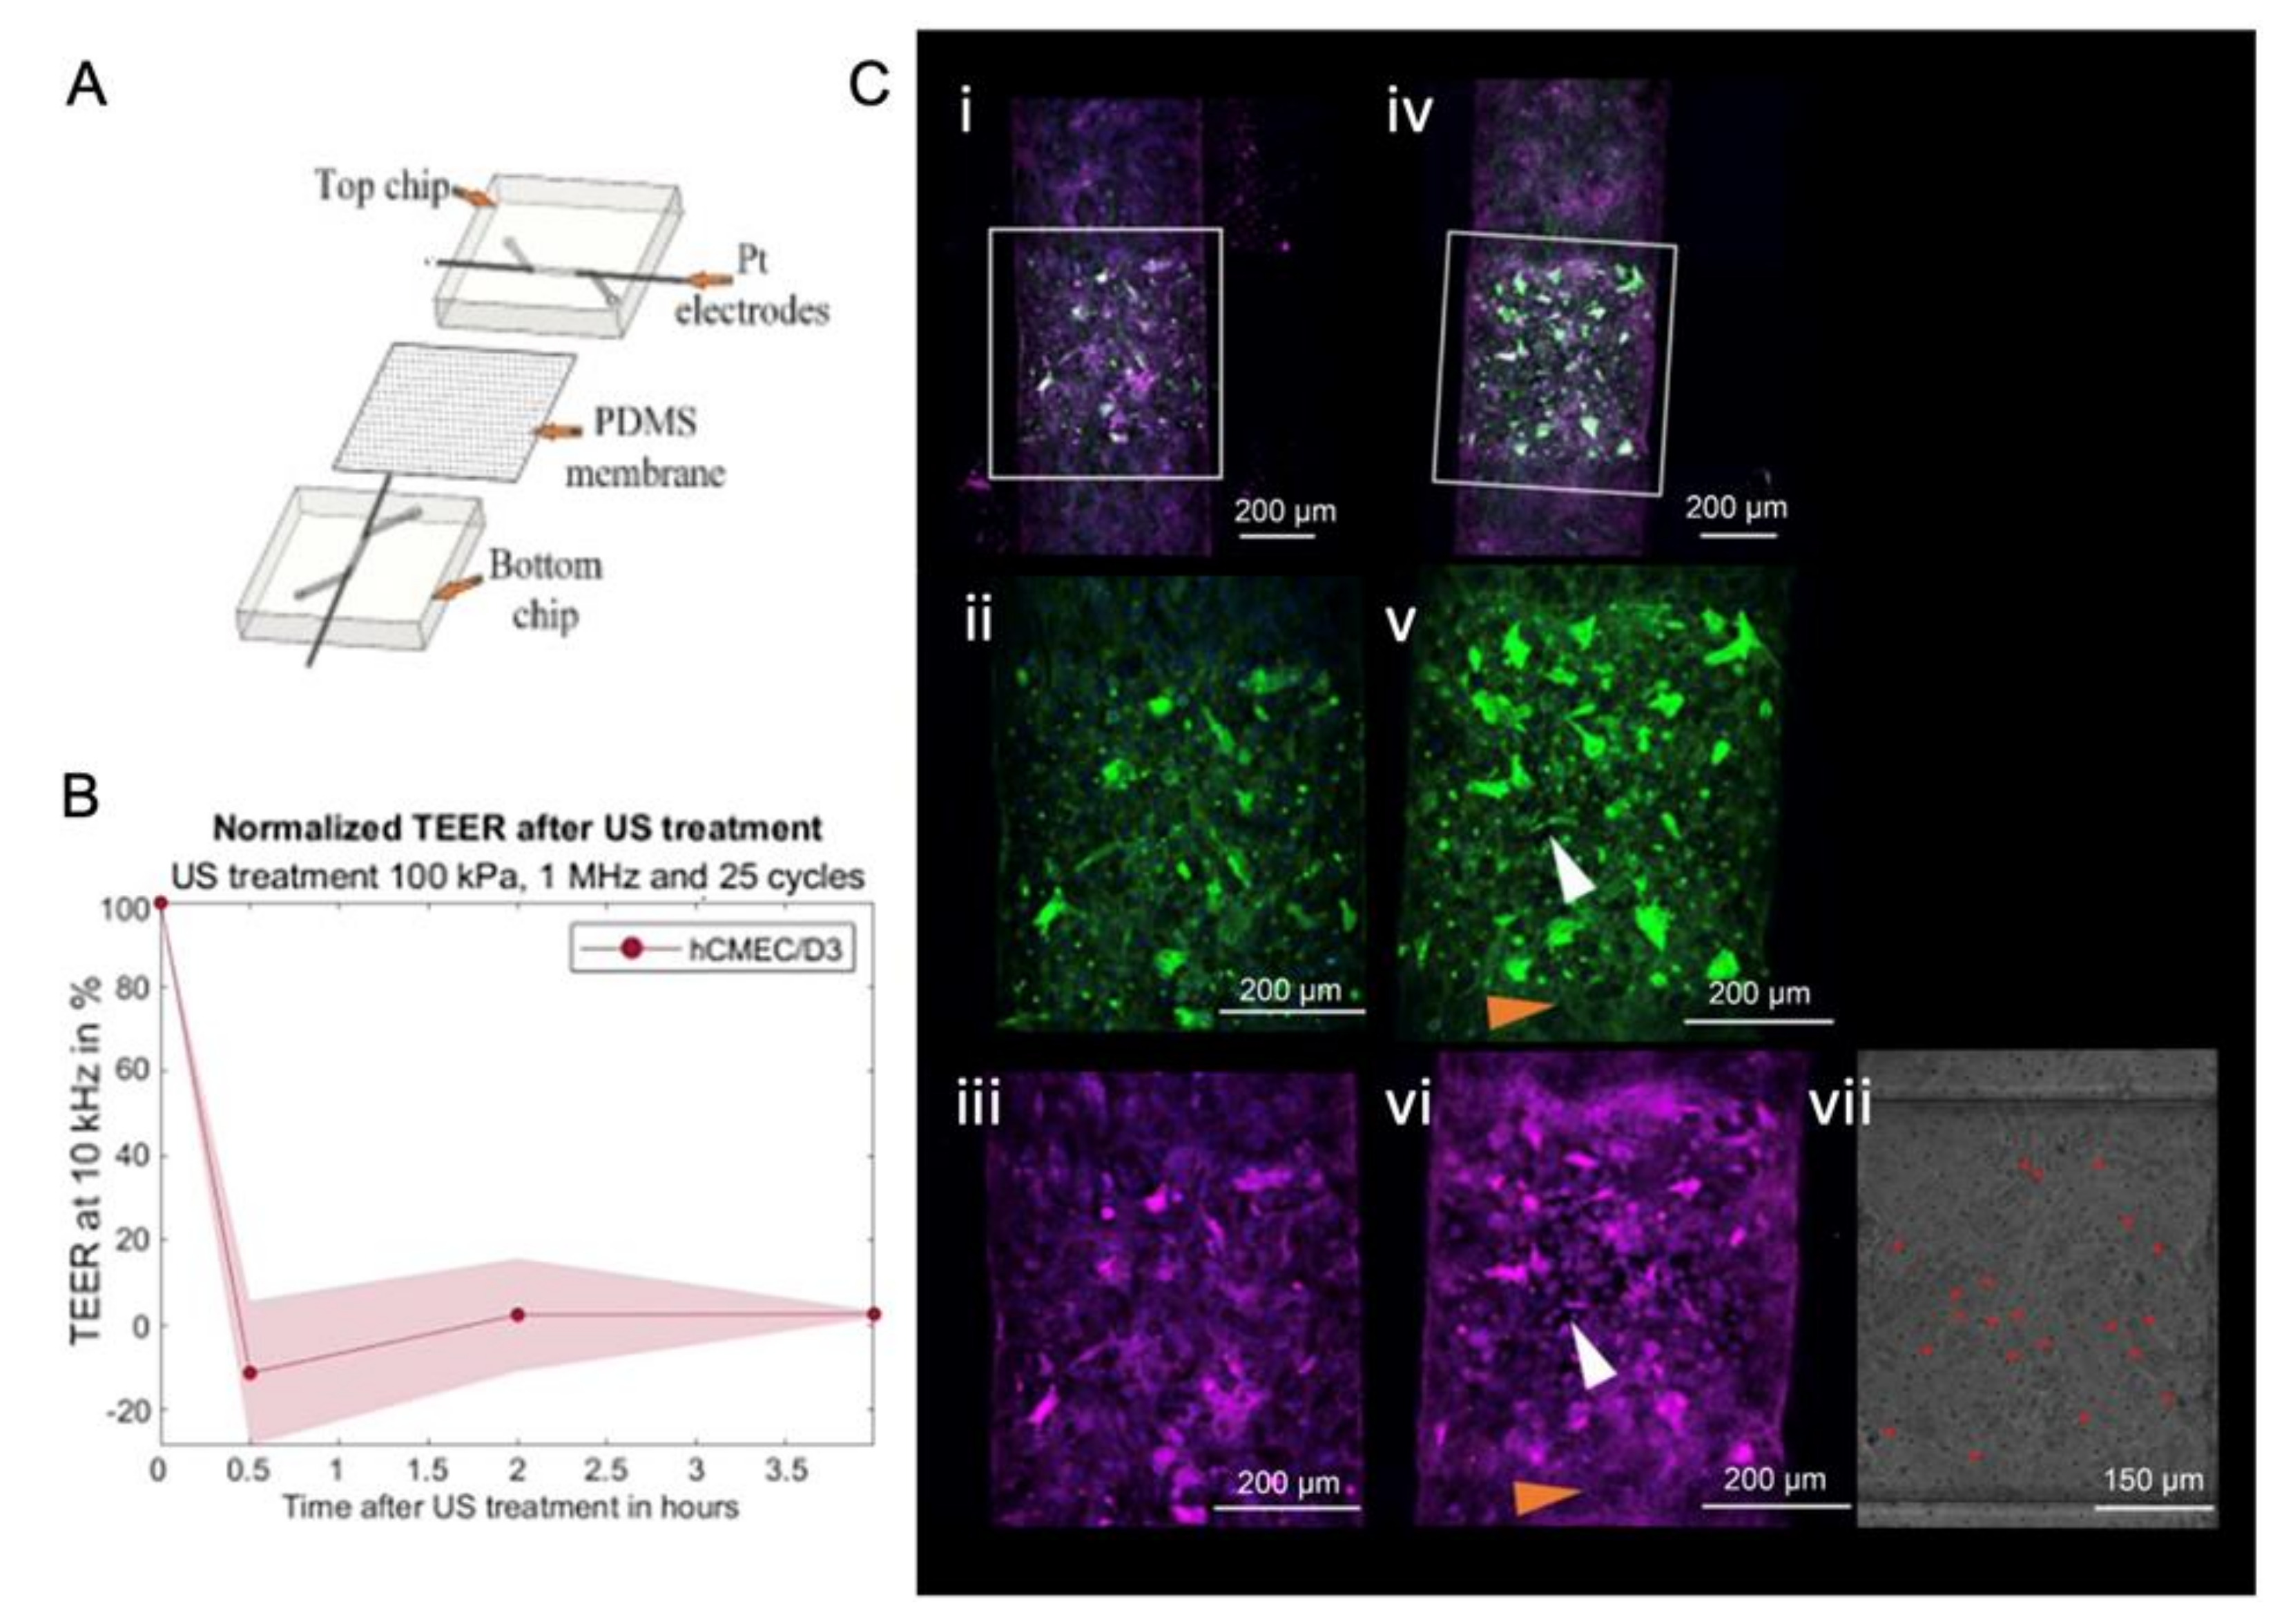

4.2.2. In Vitro Static System

4.2.3. In Vitro Dynamic System